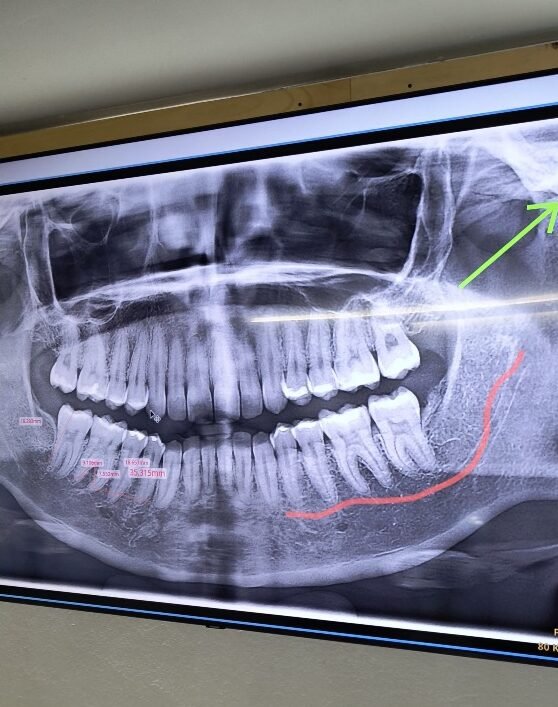

1. Estudio digital completo

Se realiza una evaluación detallada con:

Tomografía 3D (CBCT)

Escaneo intraoral

Fotografías clínicas

Análisis de la zona donde irá el implante

Con esta información determinamos el tipo de injerto que necesitas y la cantidad exacta de regeneración requerida.

Las radiografías por ejemplo son con una camarita de baja radiación. Muy recomendable